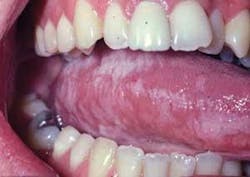

Distingishing characteristics: The plaque does not wipe off with gauze. There is no bleeding or raw surface that is sometimes found with candida when wiped with gauze. However, candida may occur in conjunction with HL (see Figure 3).